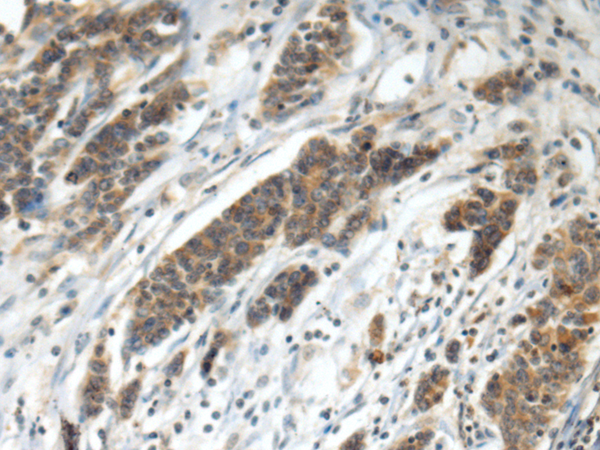

IHC positive control: |

Human colorectal cancer |

IHC Recommend dilution: |

100-300 |